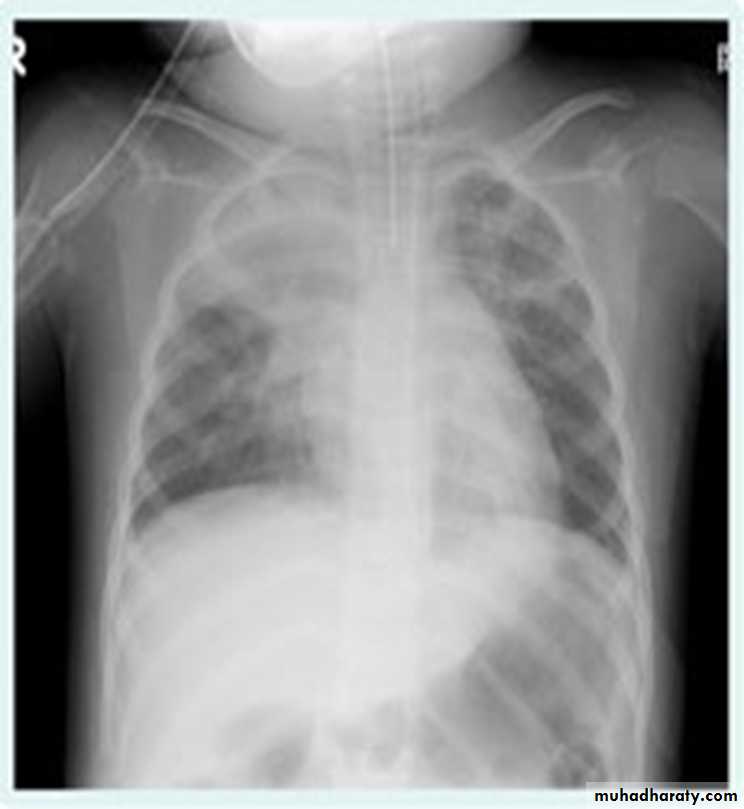

Pleural effusion

50.pleural effusion

51.pleural effusion .